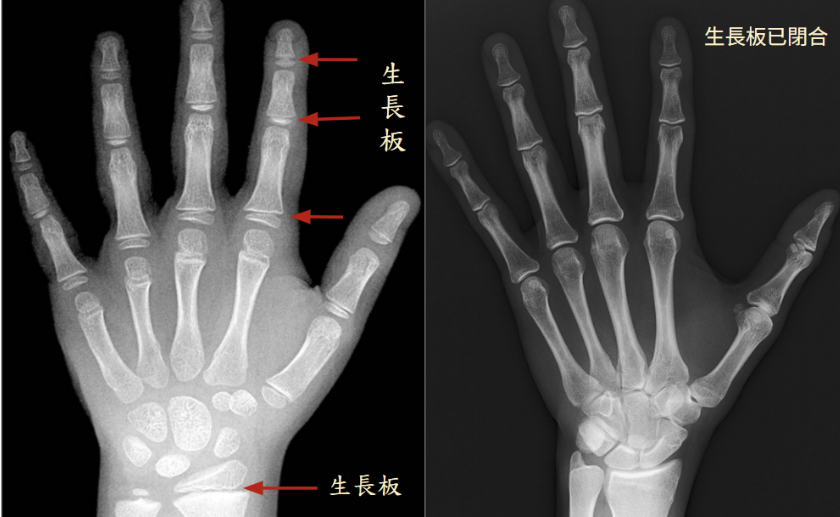

生長板(growth plate),又稱骨骺板(epiphyseal plate)

生長板位於人體長骨末端,例如手指、手臂、大腿骨、小腿骨等末端均有由軟骨組織構成的生長板,生長激素刺激生長板幫助長高;X 光能穿透軟組織,因此生長板在 X 光影像上呈現較暗的黑色區域;相對地,無法被穿透的硬組織(如骨骼)則會顯示為明亮的白色影像

骨齡攝影檢查

每個人身高的增長關鍵在於骨頭成長的情形,這個的關鍵就是生長板(growth plate),又稱骨骺板(epiphyseal plate),一旦生長板癒合表示骨骼成長結束,人體將不容易再增高、目前常用來比對年齡。 評估骨骼成熟程度的檢測方式即為骨齡攝影檢查(bone age study)。